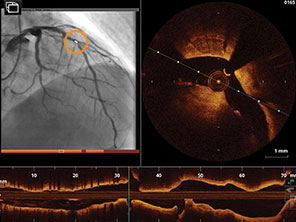

• Hệ thống Hình ảnh OPTIS™ là một hệ thống tích hợp OCT cao cấp và đo lường sinh lý mạch máu động mạch trên cùng một nền tảng, giúp hỗ trợ quyết định trong quá trình thực hiện PCI (phẫu thuật can thiệp đặt stent).